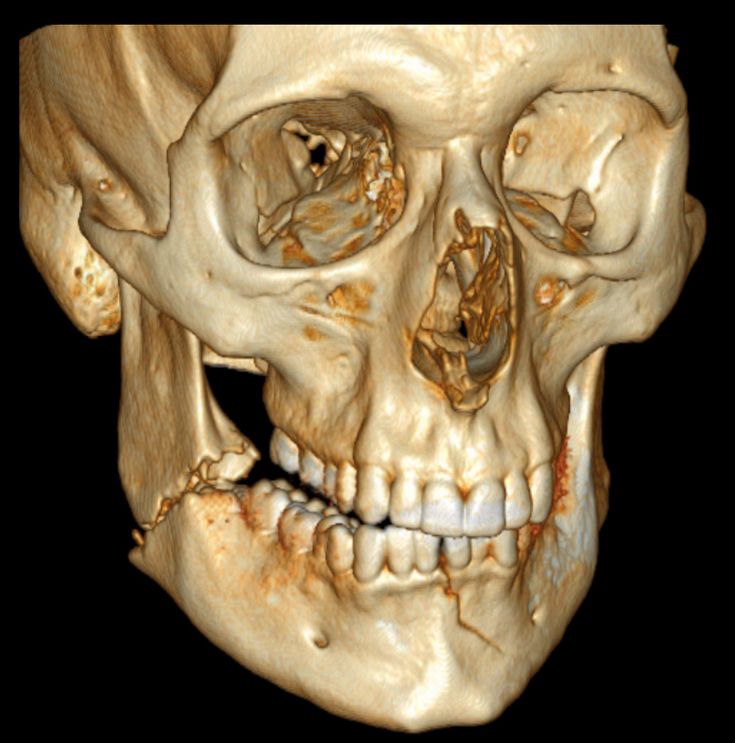

trauma facial

Diagnóstico y tratamiento de traumatismos (fracturas, contusiones) del esqueleto facial (órbitas, hueso maxilar y mandíbula).

CBCT (Cone Beam Computed Tomography) es una técnica imagenológica que permite obtener imágenes tridimensionales del esqueleto maxilofacial, el interior de la estructura dental y el grado de reabsorción ósea que en muchas ocasiones no es apreciable con una radiografía convencional. Igualmente, resulta de gran ayuda para poder descubrir lesiones de todo tipo que estén relacionadas con el hueso, bien sean quistes o tumores, fracturas y procesos infecciosos.

El escáner CBCT nos reporta múltiples beneficios en comparación con otras técnicas. Algunas de las ventajas que podemos apuntar de una exploración de CBCT:

• Tiene una calidad de escáner de imagen muy elevada.

• Se trata de una práctica rápida, se completa en aproximadamente 2 minutos.

• El escáner realiza imágenes desde muchos ángulos, que pueden ser manipuladas digitalmente, permitiendo una evaluación más completa.

• La radiación a la que debe someterse el paciente es muy baja. La dosis de una tomografía convencional es igual a la recibida en 75 CBCT.

• Se puede observar el tejido blando y el tejido óseo a la vez.